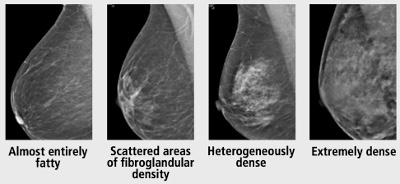

👉Debate on adjunct screening in women with dense breasts has resulted from legislation mandating that women be informed if their mammograms show dense breast tissue, including informing them that other screening modalities are available.